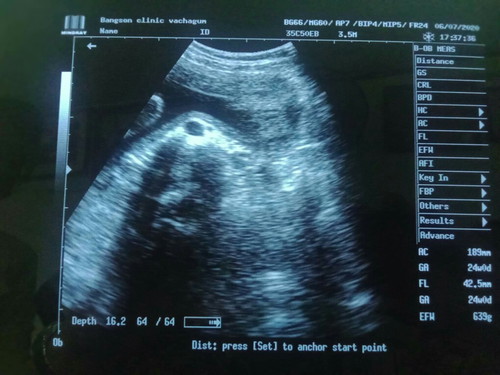

แม่ๆช่วยดูหน่อยนะค่ะว่าน้องผู้หญิงหรือผู้ชาย หมอบอกน้องหนีบไว้แต่หมอมั่นใจว่าเป็นผู้หญิง 80%

บ้านนีตอนท้องลูกก็หนีบไว้เหมือนกันค่ะ หนีบทั้งขาปิดทั้งหน้ายันคลอด หมอก็เดาว่าน่าจะผู้ญ ลุ้นตอนคลอดสรุปเป็นผู้ญ ค่ะ